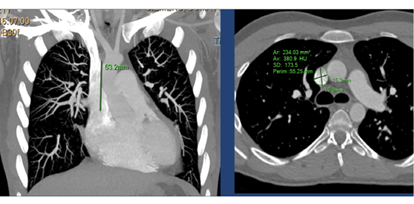

- Cross sectional CT or MRI to measure the SVC diameter, number of anomalous pulmonary veins, site of anomalous drainage (high SVC, SVC-RA junction) and Qp:Qs (Figure 1)

Figure 1

Note the slightly more gradual curve compared to the 5 Fr. RCA